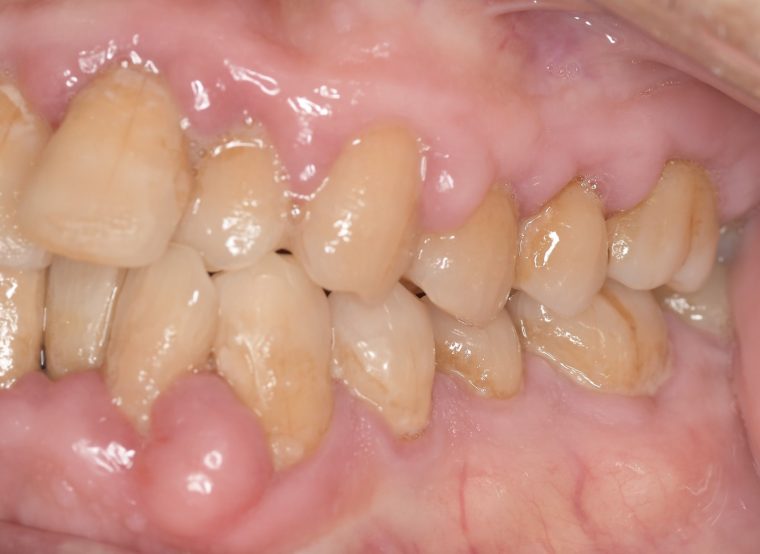

CASE 14

下顎before

下顎after

臼歯before

臼歯after

基本情報

| 年齢・性別 | 27歳・男性 |

|---|---|

| 主訴 | 歯石とりたい |

| 治療内容 | スケーリング |

| 治療期間 | 30分 |

| 治療費 | 約1,500円(保険診療) |

| リスク・副作用 | 知覚過敏、歯肉退縮、出血 |

| 治療方針 | 歯列不正でプラークがつきやすいため、TBIを行い定期的に歯石を除去していきます。 プラークコントロールが出来るようになったら定期検診でクリーニングを行っていきます。 |